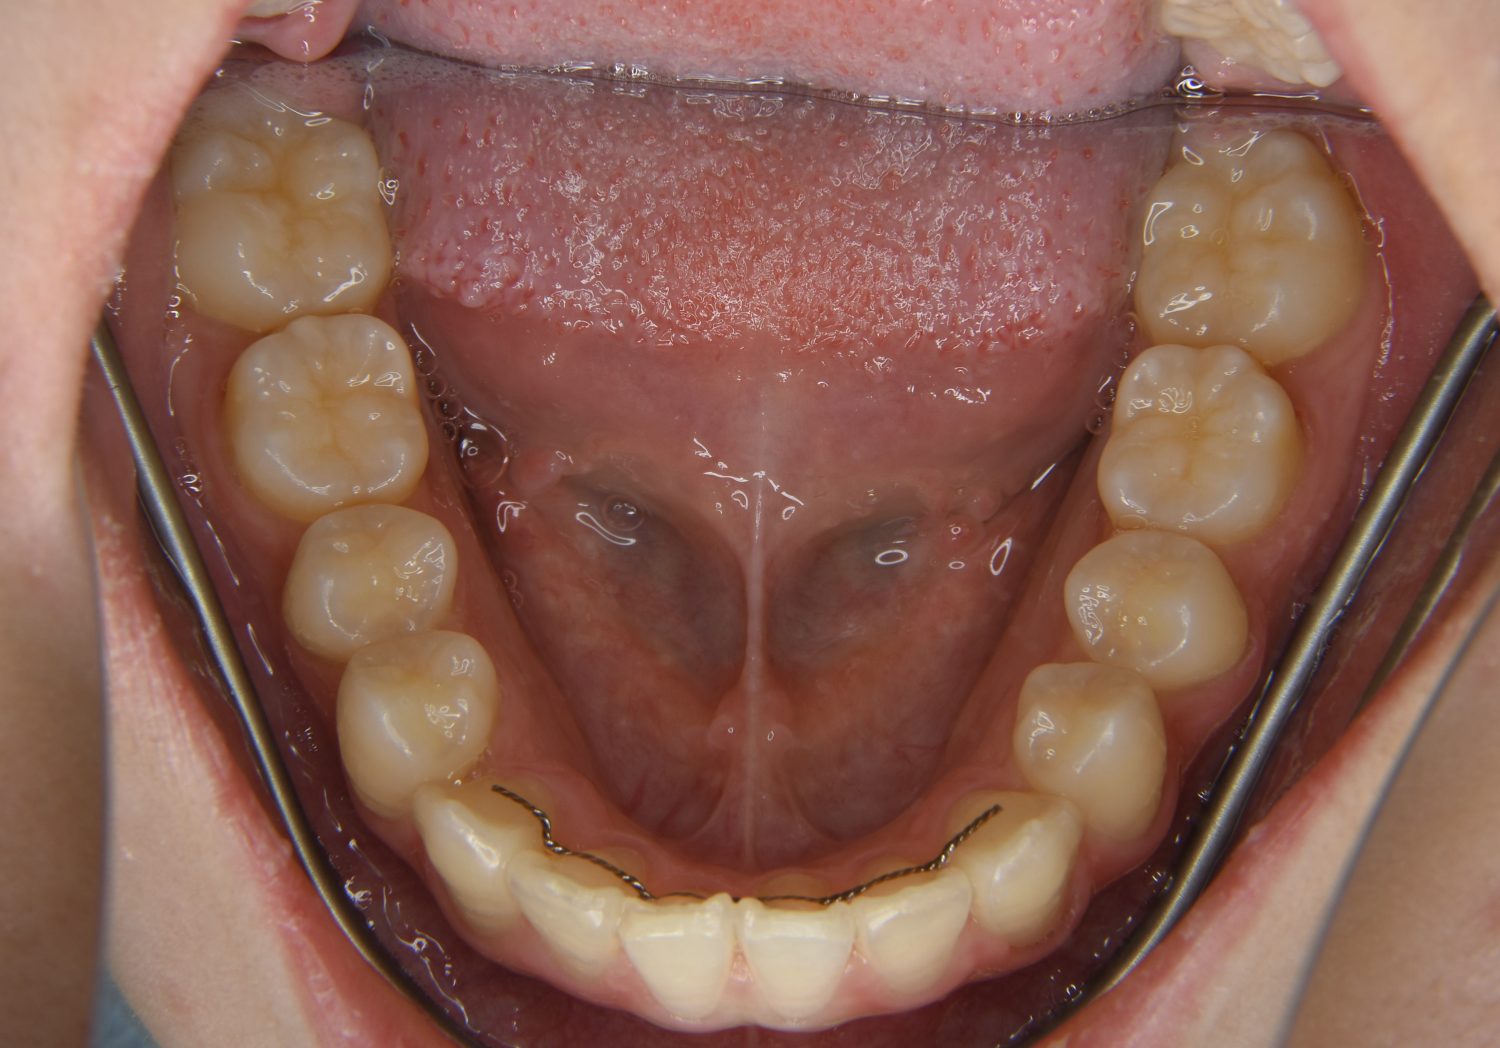

叢生の症例紹介②

Before

After

主訴

歯の凸凹を治したい。

治療内容

アライナー(インビザライン)にて非抜歯で治療を行いました。

治療費

1,150,000 円(税込)

治療期間

26ヶ月

通院回数

14回

想定されたリスク

※歯根吸収、歯肉退縮、歯髄壊死、顎関節症状

※アライナー(インビザライン)は日本の薬機法未承認の矯正装置であり、医薬品副作用被害救済制度の対象外となる場合があります。

丸山和宏先生

ピーススマイル矯正歯科

上下前歯部に叢生(凸凹)が認められる状態でした。歯列の遠心移動を行うことで機能面および審美面が改善されました。